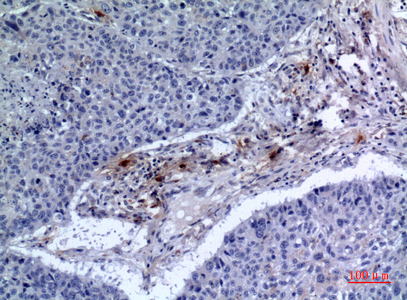

Immunohistochemical analysis of paraffin-embedded human-lung, antibody was diluted at 1:100